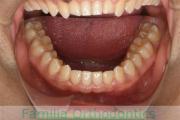

下顎

前歯の関係など

右側

正面

左側

歯並びを治したいということで来院されました。下あごがやや右側に偏位して後退している、上顎前突(出っ歯)でした。上下左右から小臼歯を抜歯して、歯科矯正用アンカースクリューを併用したマルチブラケット法にて治療を行いました。約2年、24回の来院をしていただきました。

下顎の後退はいびきなどの上部気道の障害が出やすいと考えられます。